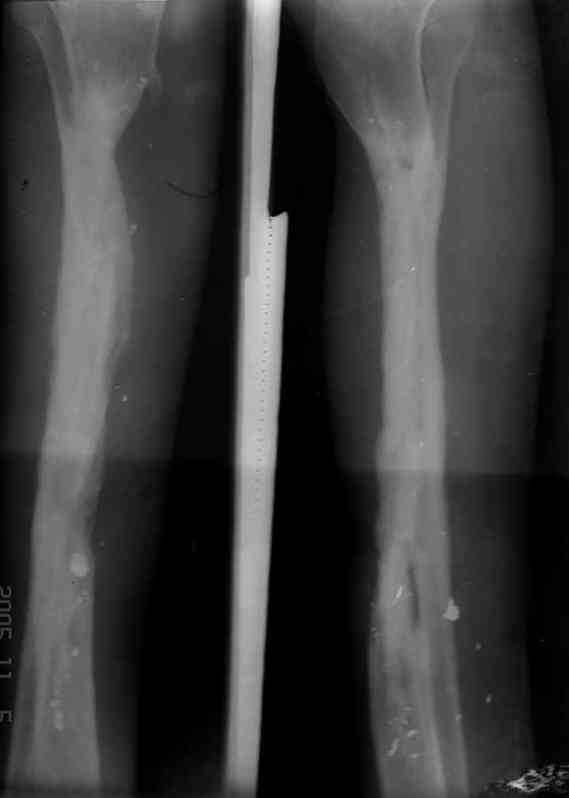

Реализовал описанную выше методику, и в итоге вот что получилось. Высылаю лишь прямые проекции,

в боковых тоже всё в тему.

Очень пригодились карбоновые кольца (Джолдас -огромное спасибо, я твой должник!!!), поскольку остеопороз дистального отломка был просто невероятный. На цифровом рентгене с трудом угадывались контуры.

Рентген в процессе перемещения - внизу карбоновые кольца, тракция фрагмента спицами с упором.